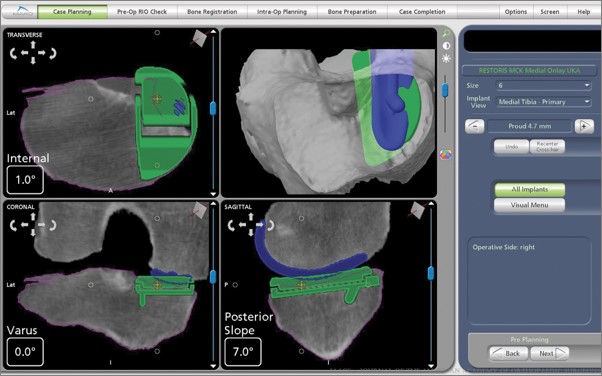

Robotic-assisted joint replacements instead combines three-dimensional planning before surgery with real-time computer navigation during surgery. Using robotic tools that have sensory feedback, the surgeon can remove damaged bone and cartilage and implant artificial joints with greater precision, as well as help to preserve healthy tissue.

For a robotic procedure, special imaging is often obtained before surgery to create a customized 3-D plan for your joint replacement, depending on which robotic platform the surgeon uses.

- The ability to create a customized surgical plan and choose the ideal implant sizes before surgery

During the surgery, your surgeon will place navigation pins into your bone to guide the robotic-assisted instruments in space. The robotic instruments provide sensory feedback to assist the surgeon in precisely removing damaged bone and cartilage and replacing it with prosthetic (artificial) components.